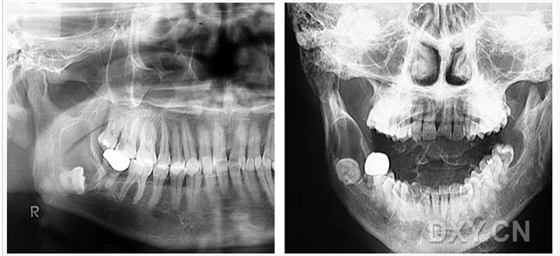

成釉細胞瘤